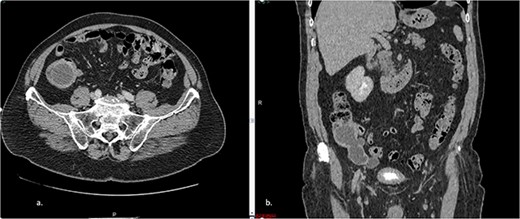

The abdominal CT scan showed cystic distension of the cecal appendix with a maximum diameter of 3.6 cm, accompanied by intussusception into the cecum. The anterior wall of the appendix showed irregular thickening close to the transition of the middle/distal third (Fig. 1). The colonoscopy revealed a mount-like elevation of the appendix orifice, also known as the ‘volcano sign’. The patient’s laboratory test results showed a mild elevation of the cancer-associated antigen 19–9 (52 U/ml), with normal levels of CEA and white blood cells (WBC). The patient’s renal function and electrolyte levels were within normal limits.

a. Axial CT section of the abdomen showing signs of mucocele of the appendix with intraluminal air. b. The coronal CT section of the appendix shows that the anterior wall of the appendix had an irregular thickening close to the transition of the middle/distal third.